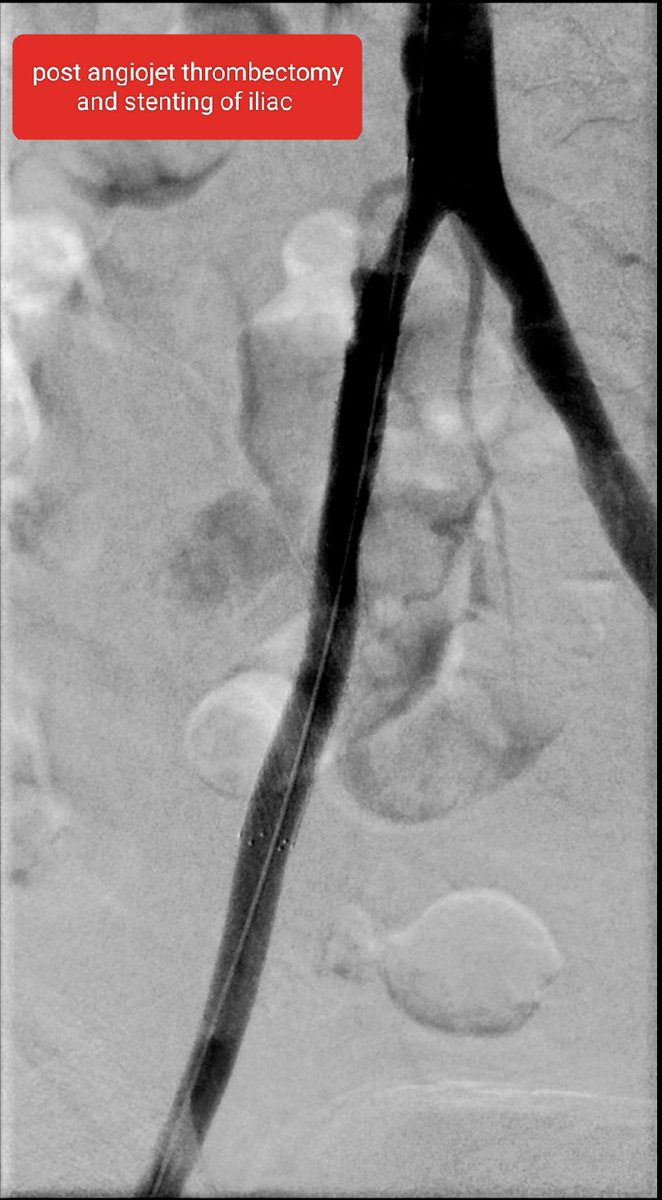

@rahilkassamali

Iliac occlusion crossed - felt to be acute on chronic. Angiojet pulse spray 10mg in 100ml Angiojet thrombectomy 100s Iliac thrombus cleared and underlying stenosis identified. 10mm X 8cm bare metal stent deployed. TPA infusion left for SFA and pop thrombus